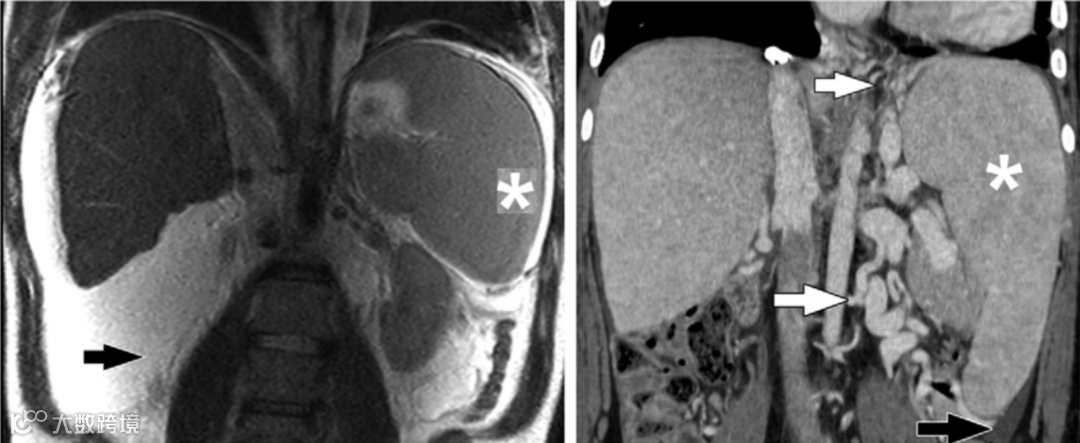

Zafar F, Lubert AM, Trout AT, et al. Abdominal CT and MRI Findings of Portal Hypertension in Children and Adults with Fontan Circulation. Radiology 2022.

简评丨张金山